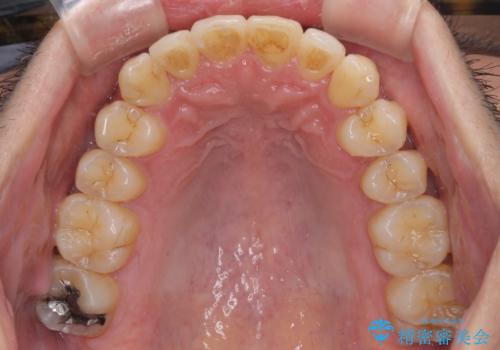

前歯のデコボコ ワイヤー装置での短期間治療

- 前歯のデコボコを気にして来院された患者様です。

インビザラインまたはワイヤー装置、どちらでも対応可能でしたが、自己管理の少なさ、期間の短さから、ワイヤー装置による矯正治療を行うこととしました。

治療開始の頃は、食事や歯磨きが慣れず、装置が頻繁に脱落しましたが、2,3ヶ月ほどで慣れ、その後は1年ほどで治療を終えることができました。